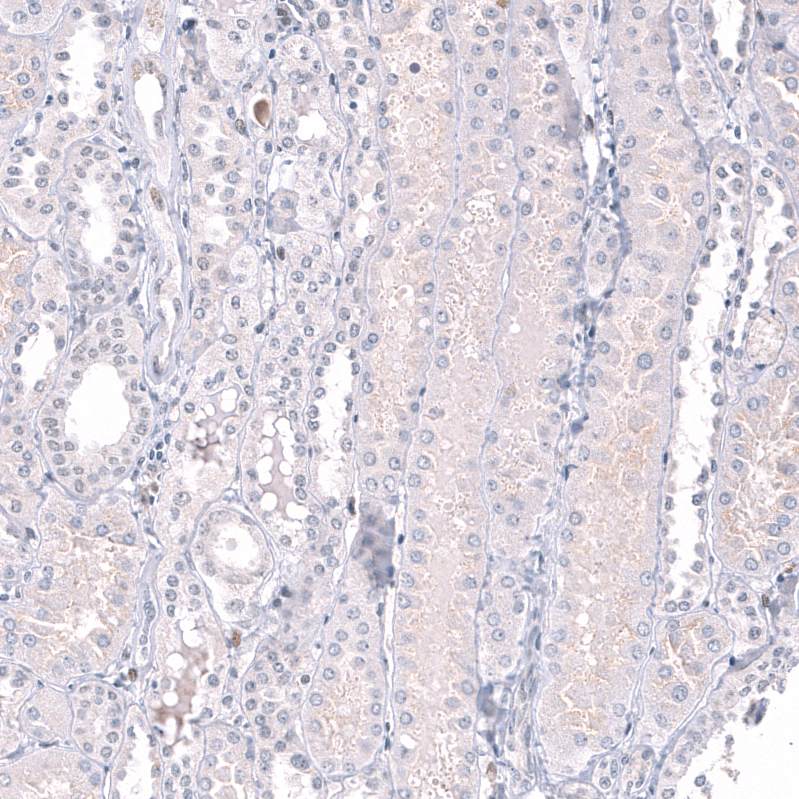

Immunohistochemistry analysis in human testis and cerebral cortex tissues using AMAb91750 antibody. Corresponding EZH2 RNA-seq data are presented for the same tissues.